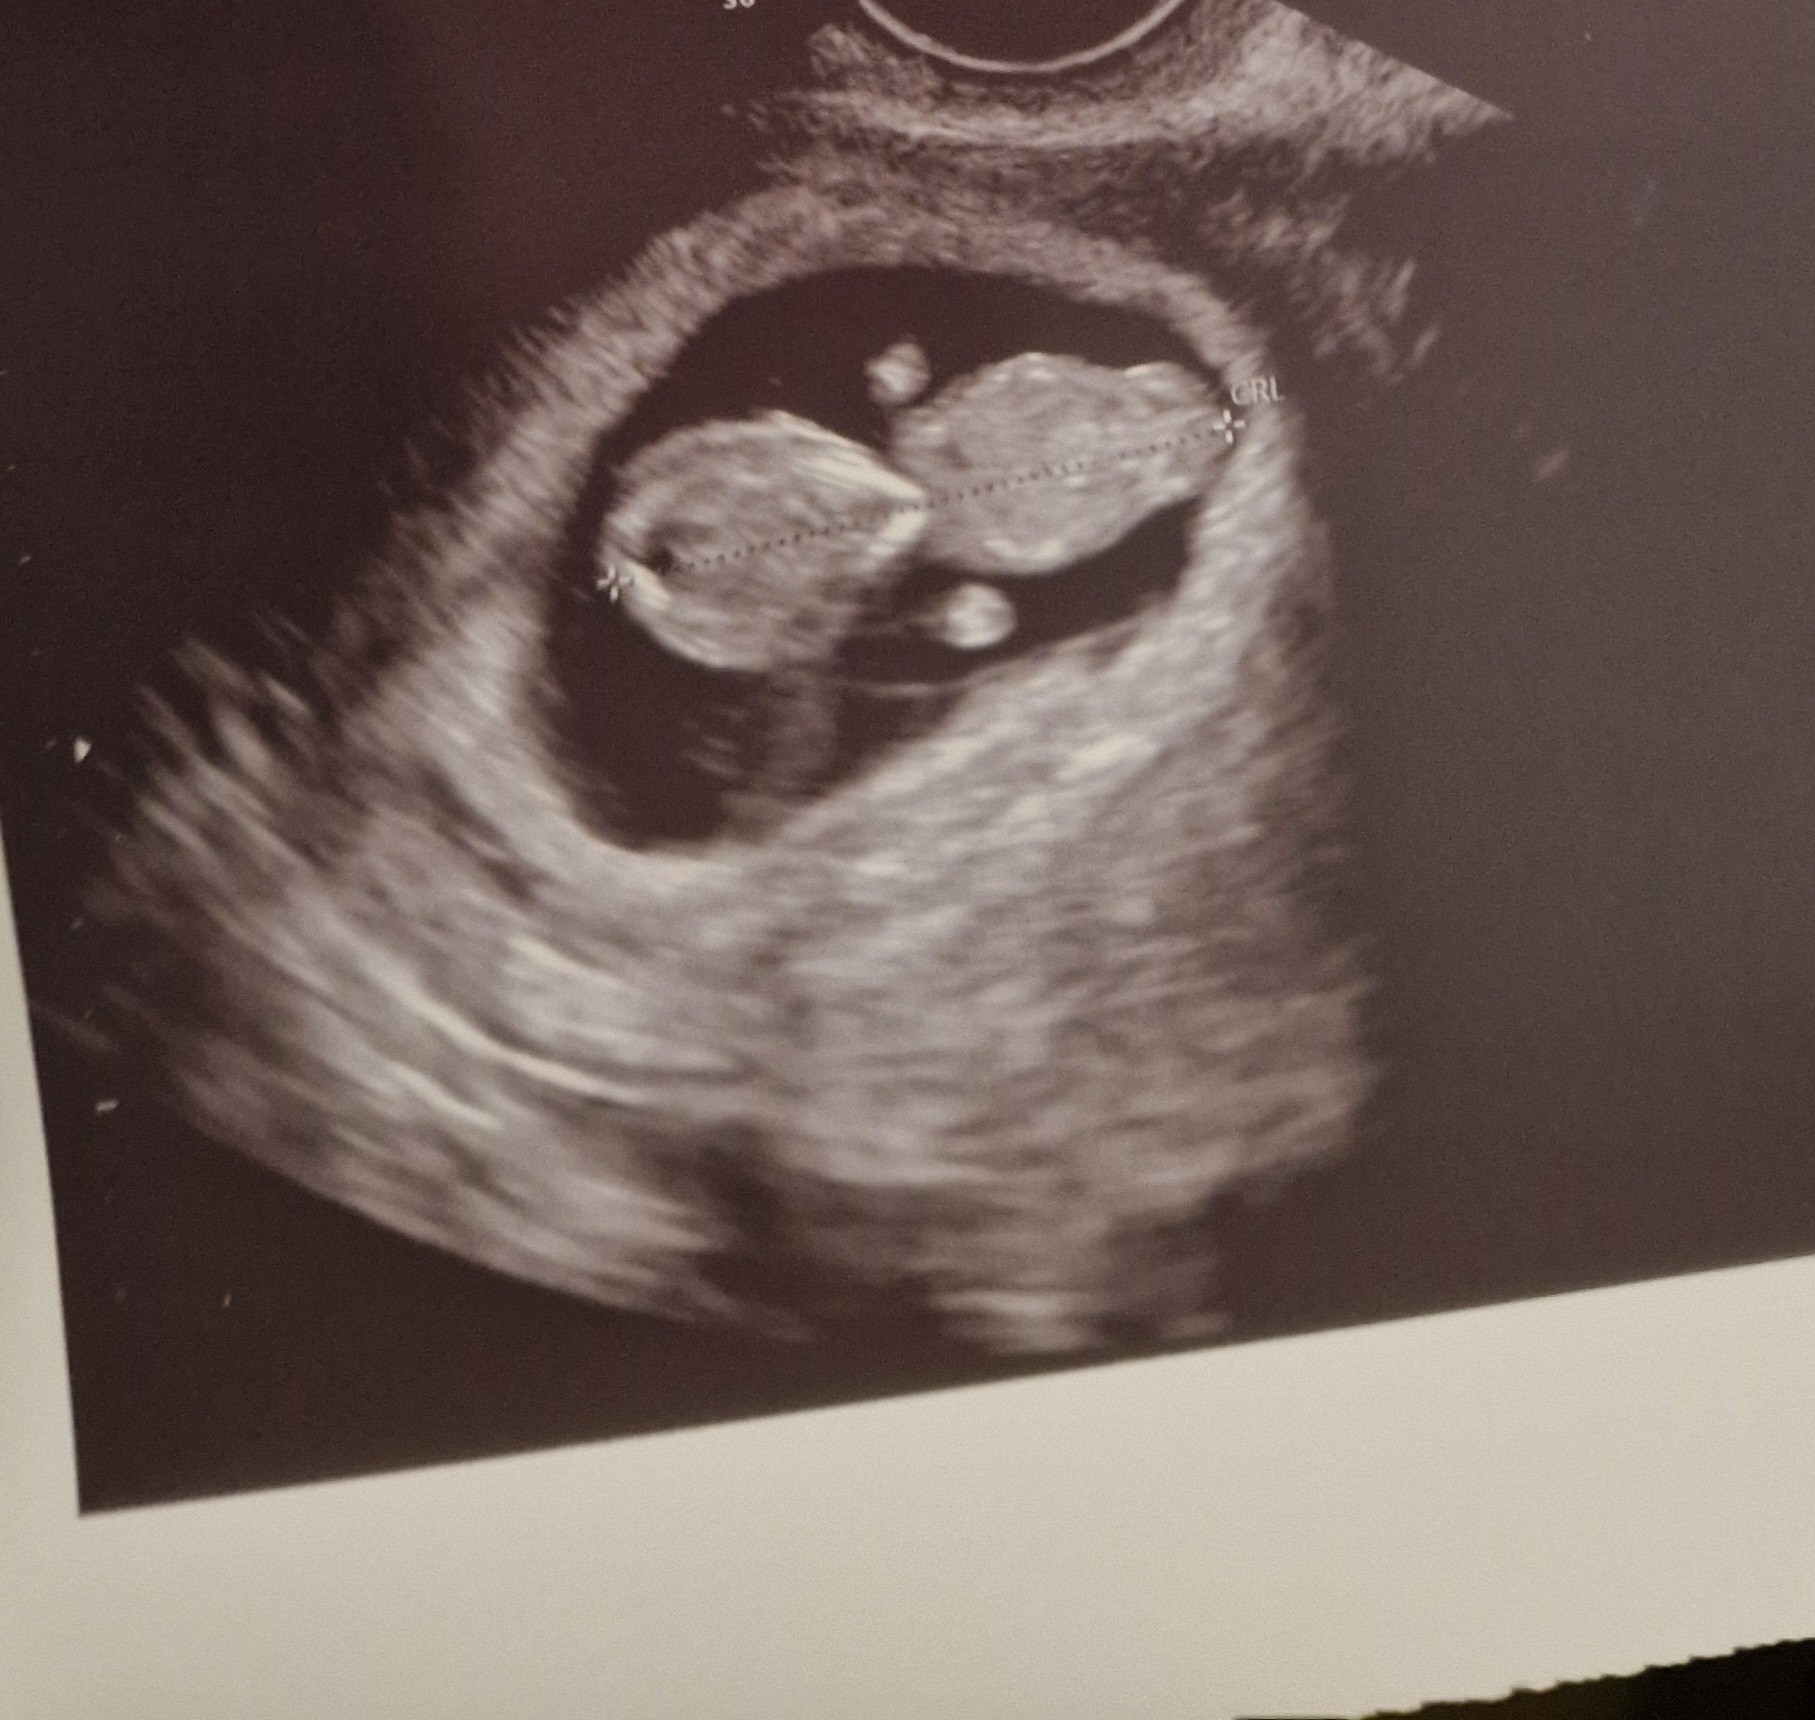

Jest prawie 4 cm człowieczka. Serce bije pięknie, dziś je pierwszy raz usłyszałam.

Skakał sobie troszkę w tym brzuchu, widać już mu dobrze rączki i nóżki.

Moja słodka bułeczka !! 🥹